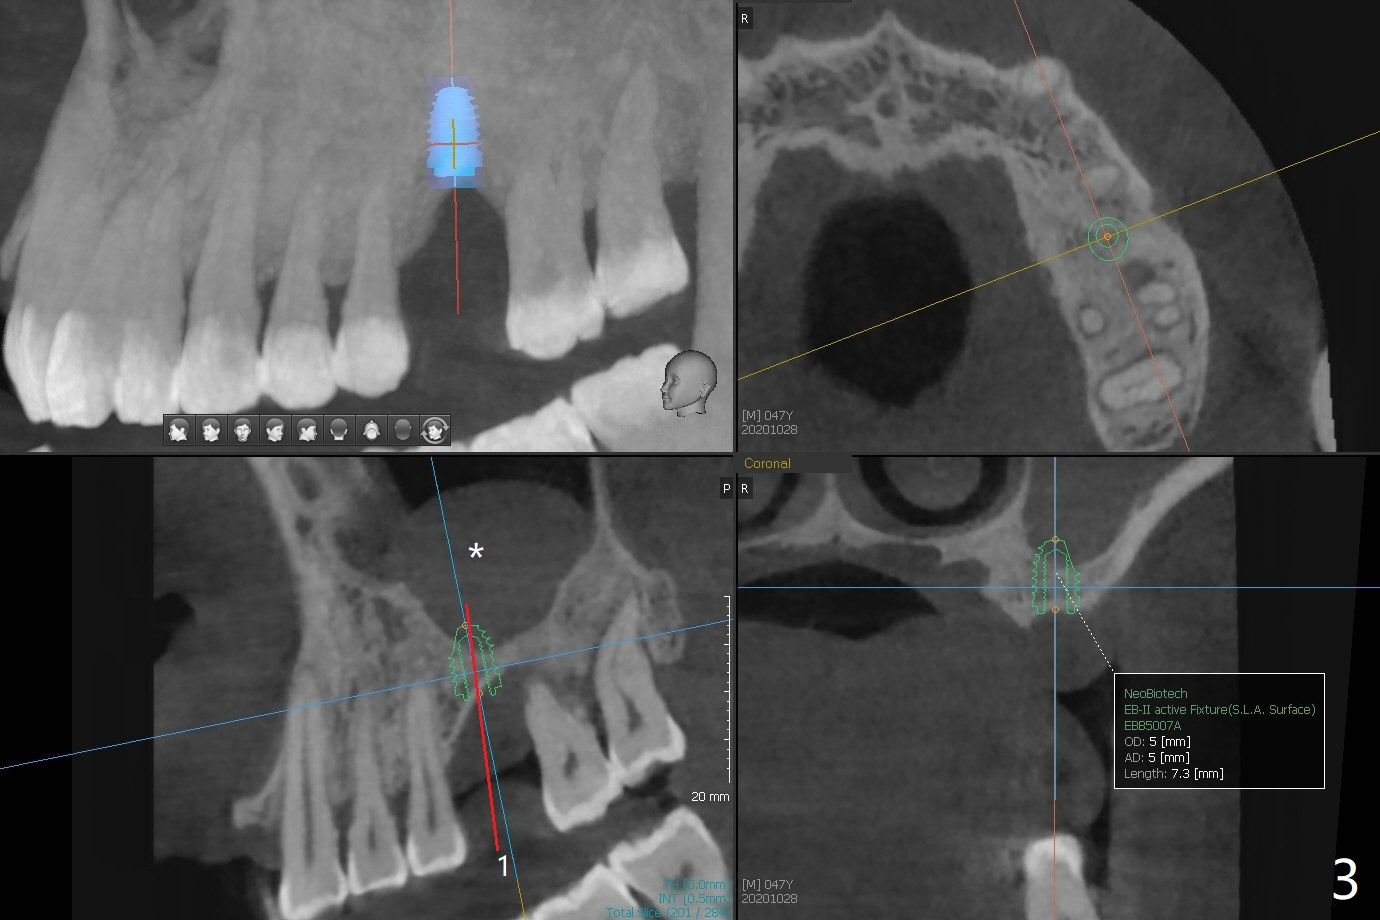

47岁男(吸烟一天半包)因右下8疼痛就诊,口服抗生素疼痛消失,不愿意拔除,但是要求左上6植牙(图一),左上颌窦好像有粘液囊肿(图一,三:*),而右侧上颌窦粘膜更厚(图二)。左上6植牙床是一个斜面,植牙会远中偏移,导板设计应有意往近中(图三:红线)。植体远中根尖需要内提升,冠部需要植骨(图四),厚的粘骨膜有利于植骨(粘骨,使用mill abutment),骨粉尽可能放置7牙根近中(图五:红色圆圈,Endogain)。第二种设计(图六)使用细长植体,近中龈下4毫米,远中龈下8毫米,有利于植骨,覆盖远中暴露的螺纹。Return to No Caries 位点保存/导板 手术 提升 Xin Wei, DDS, PhD, MS 1st edition 10/28/2020, last revision 04/04/2021